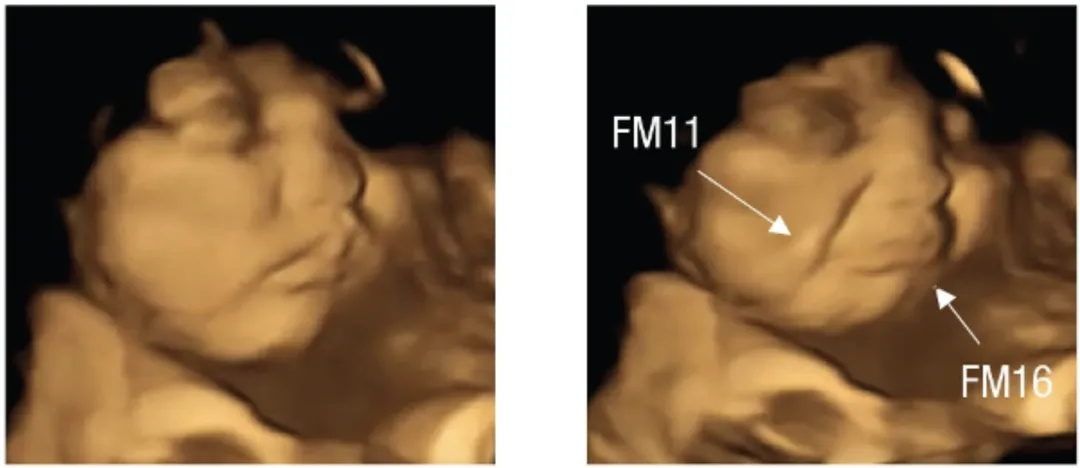

宝宝还在妈妈肚子里时,就能够通过羊水「尝」到味道。有研究显示,在怀孕最后三个月喝胡萝卜汁的孕妈,生下的宝宝会比同龄婴儿更喜欢胡萝卜味[10]。

胎儿正常表情 VS「尝」到羽衣甘蓝后的表情

图片来源:参考文献[11]